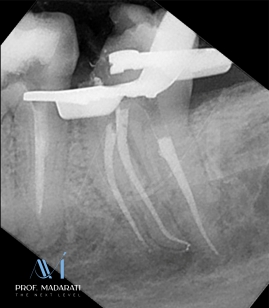

Cleaning and Shaping:

All canals were then cleaned and shaped using Chameleon Dual Shaper (Denco) in sizes 20/.04 and 25/.04.